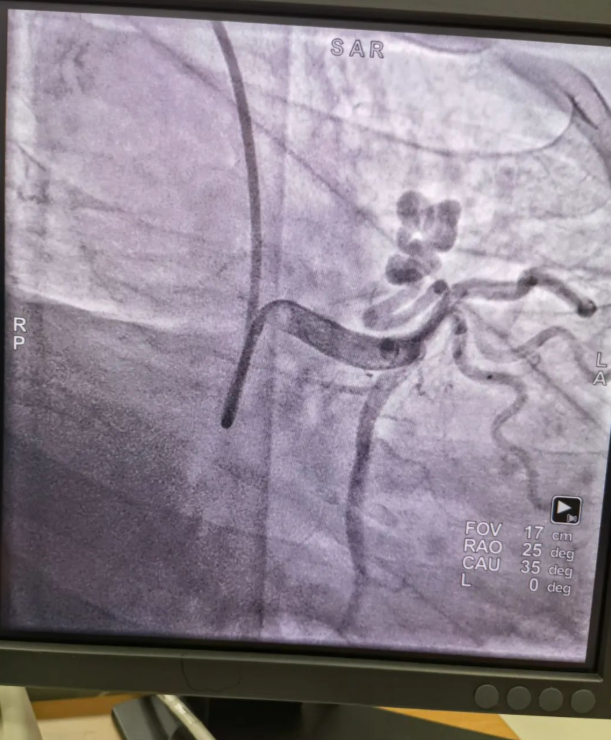

不久前,來(lái)自新疆的患者石先生去年至今反復(fù)胸悶、氣短、胸痛,就診于新疆某院,懷疑“冠心病”,住院行冠狀動(dòng)脈造影術(shù),石先生造影提示“冠狀動(dòng)脈肺動(dòng)脈瘺”,而他并非“冠心病”,所以給予的“冠心病”治療,效果不佳。出院后仍反復(fù)出現(xiàn)胸痛、胸悶、氣短等癥狀,經(jīng)親友介紹了解到西安國(guó)際醫(yī)學(xué)中心醫(yī)院心臟病醫(yī)院心臟內(nèi)科二病區(qū)曾廣偉主任,多年來(lái)潛心研究心臟病介入治療,成功主刀救治了許許多多高危復(fù)雜病例,尤其是在先心病及結(jié)構(gòu)性心臟病封堵,以及冠心病、心律失常射頻消融及起搏治療等方面積累了豐富的診療經(jīng)驗(yàn)。

此病例罕見(jiàn),在曾廣偉從醫(yī)18年生涯里曾碰到有2個(gè)印象深刻的病例,患者分別是53歲和66歲,當(dāng)時(shí)建議患者入院進(jìn)行動(dòng)脈瘺的封堵術(shù),但患者和家屬考慮到這個(gè)手術(shù)案例極少,風(fēng)險(xiǎn)也高,均未接受手術(shù)治療建議,只是能采取藥物保守治療,出院后隨訪得知患者癥狀緩解效果不佳,后來(lái)在隨訪中也與53歲患者失去了聯(lián)系,而66歲患者因冠狀動(dòng)脈肺動(dòng)脈瘺出現(xiàn)反復(fù)心衰,在當(dāng)?shù)蒯t(yī)院藥物治療,短短2年時(shí)間,患者因?yàn)閯?dòng)脈瘺未及時(shí)手術(shù)失去了生命。所以此次患者石先生到訪,曾廣偉主任在詳細(xì)掌握病例資料基礎(chǔ)上,果斷建議進(jìn)行動(dòng)脈瘺的封堵術(shù)治療,為了提高手術(shù)成功率和精準(zhǔn)度,曾廣偉主任搜集相關(guān)診療資料,反復(fù)推演論證,經(jīng)過(guò)相當(dāng)充足的準(zhǔn)備工作,于5月18日成功進(jìn)行了封堵手術(shù),完全堵上了瘺口。

患者術(shù)后第2天,已經(jīng)沒(méi)有明顯的胸悶、氣短、胸痛等癥狀,目前身體狀態(tài)良好。本次手術(shù)曾廣偉主任及其團(tuán)隊(duì),采取從右手臂一根血管進(jìn)入,并在2小時(shí)之內(nèi)完美封堵,創(chuàng)口小,痛苦小。手術(shù)雖然難度大、風(fēng)險(xiǎn)高,相關(guān)案例也少,但是曾廣偉主任主刀即在巔峰,這樣一臺(tái)完美的手術(shù)靠的不是運(yùn)氣,是豐富的臨床手術(shù)經(jīng)驗(yàn),扎實(shí)的專(zhuān)業(yè)知識(shí)儲(chǔ)備,以及對(duì)醫(yī)療事業(yè)的孜孜追求。

冠狀動(dòng)脈瘺是指冠狀動(dòng)脈與心腔、冠狀靜脈、肺動(dòng)脈等的異常連接,是一種少見(jiàn)的先天性心臟病,發(fā)病率為1.3%。而冠狀動(dòng)脈肺動(dòng)脈瘺是冠狀動(dòng)脈與肺動(dòng)脈之間產(chǎn)生的一種血管性瘺口,導(dǎo)致冠狀動(dòng)脈里的血液流入肺動(dòng)脈里,使冠狀動(dòng)脈里血液流量減少,出現(xiàn)心肌供血不足,冠狀動(dòng)脈肺動(dòng)脈瘺會(huì)使患者出現(xiàn)胸部疼痛、胸悶、呼吸困難、頭暈、乏力等一系列癥狀,隨著疾病不斷進(jìn)展,可引發(fā)心功能的障礙和心肌缺血,肺動(dòng)脈會(huì)逐漸形成肺動(dòng)脈高壓,還可能導(dǎo)致動(dòng)脈瘤的破裂,甚至威脅病人的生命安全,所以早期發(fā)現(xiàn)和治療冠狀動(dòng)脈肺動(dòng)脈瘺,對(duì)病人的預(yù)后改善具有重要的意義。